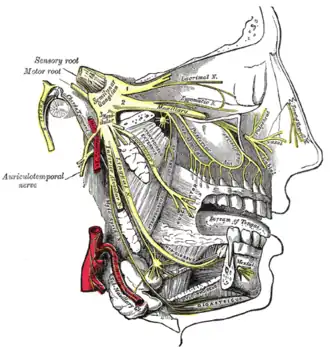

Distribution of the maxillary and mandibular nerves, and the submaxillary ganglion. (Inferior alveolar visible at center left.) | |

The inferior alveolar nerve (IAN) (also the inferior dental nerve) is a sensory[1] branch of the mandibular nerve (CN V3) (which is itself the third branch of the trigeminal nerve (CN V)). The nerve provides sensory innervation to the lower/mandibular teeth and their corresponding gingiva as well as a small area of the face (via its mental nerve).

The inferior alveolar nerve arises from the mandibular nerve.[2]: 543

After branching from the mandibular nerve, the inferior alveolar nerve passes posterior to the lateral pterygoid muscle. It issues a branch (the mylohyoid nerve) before entering the mandibular foramen[2]: 543 to come to pass in the mandibular canal within the mandible. Passing through the canal, it issues sensory branches for the molar and second premolar teeth; the branches first form the inferior dental plexus which then gives off small gingival and dental nerves to these teeth themselves.[3]

The nerve terminates distally/anteriorly (near the second lower premolar) within the mandibular canal by splitting into its two terminal branches: the mental nerve, and the incisive branch.[1]

Branches

Distribution

The inferior alveolar nerves supply sensation to the lower teeth,[2]: 519 and, via the mental nerve, sensation to the chin and lower lip.

The mylohyoid nerve is a motor nerve supplying the mylohyoid and the anterior belly of the digastric.